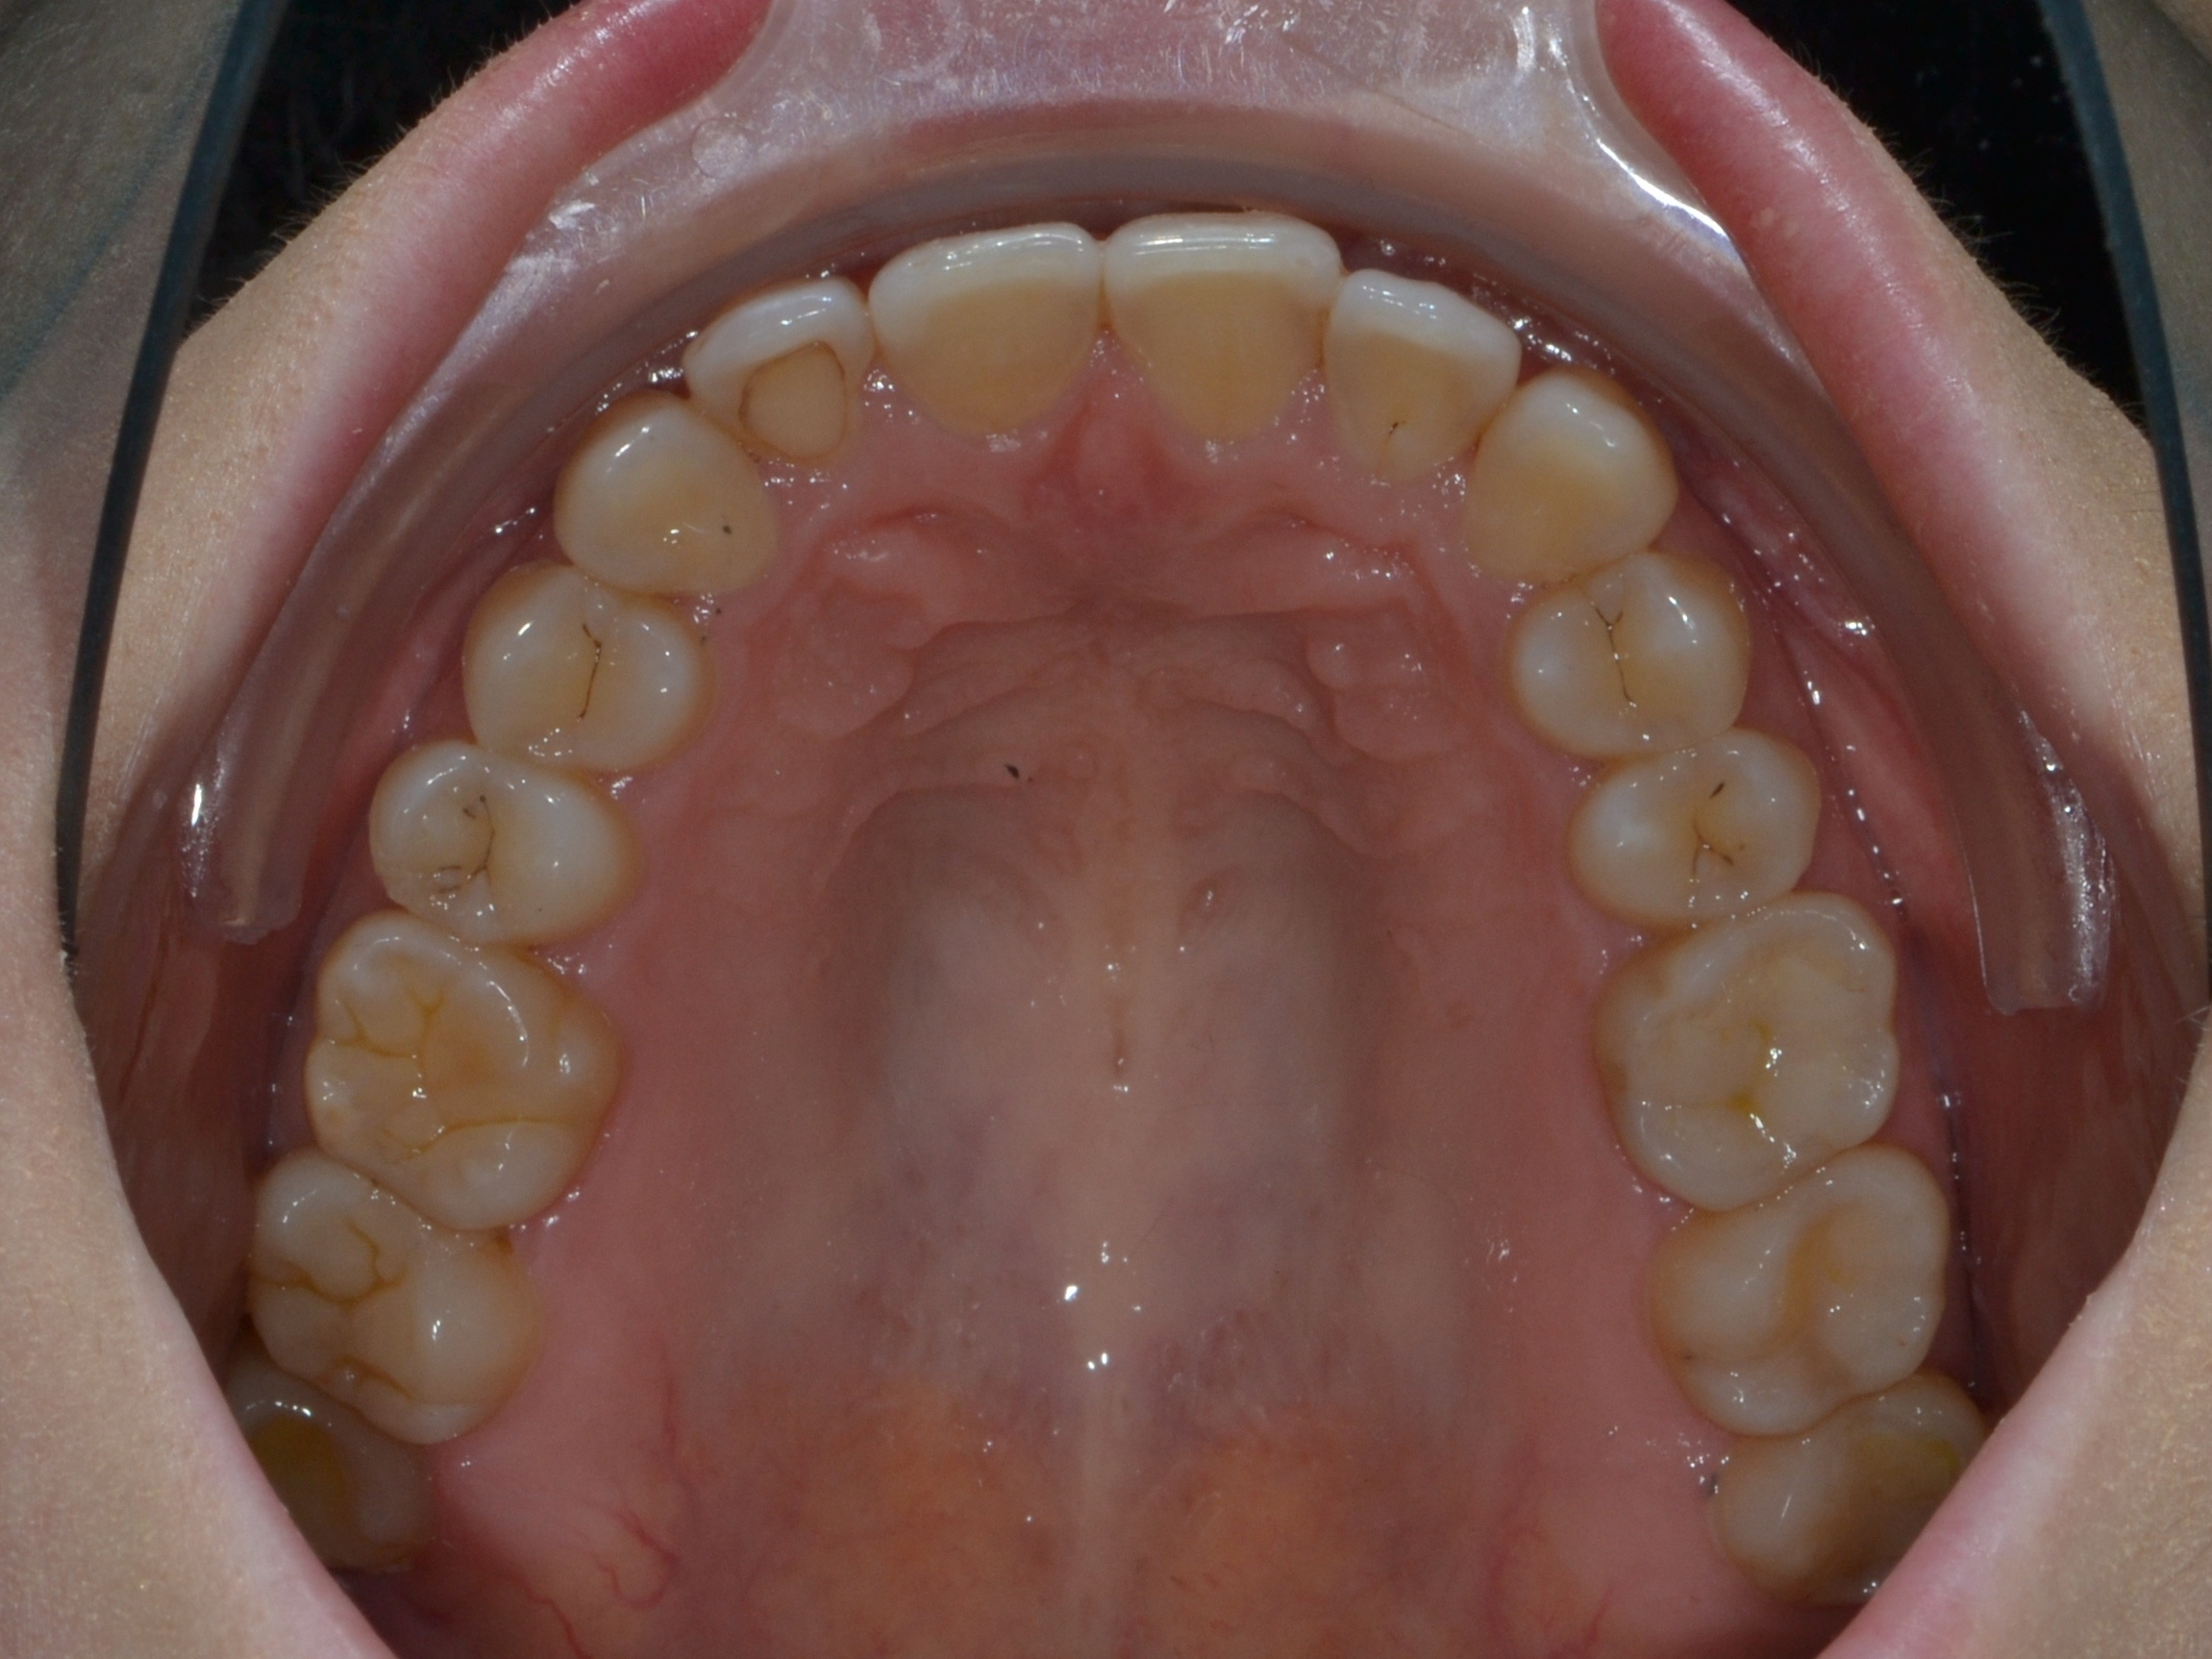

Выявленные проблемы

• Дистальная окклюзия

• Дефицит апикального базиса

• Сужение зубных рядов

• Вестибулярное положение клыков

• Скученность во фронтальных и боковых отделах

Брекет-система Pro